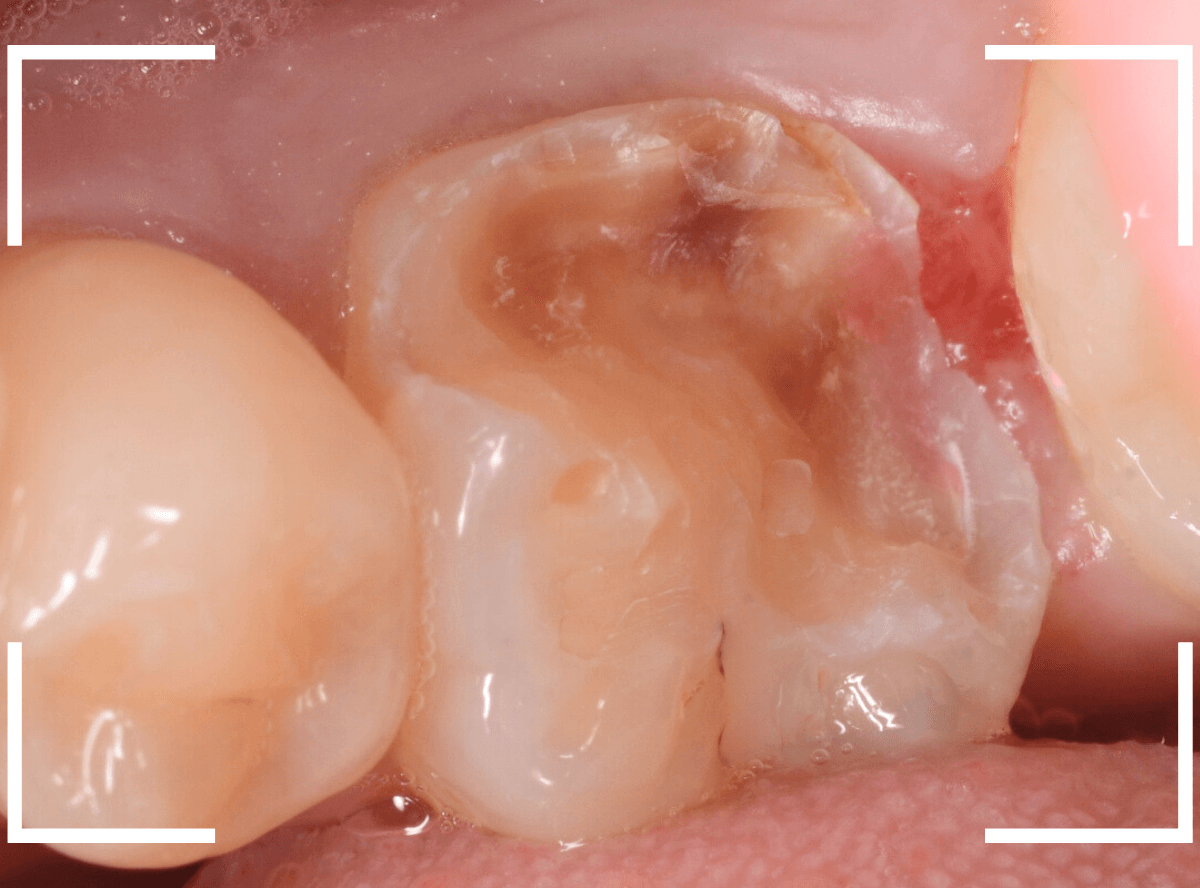

麻酔をして、治療を開始します。

レジンを外すと、中から出血してきました。

止血しながら、電気メスで歯の中に入り込んだ歯肉を除去します。

虫歯と入り込んだ歯肉でぐちゃぐちゃになっている状態でした。

これでは、痛みが出てもおかしくありません。

慎重に全ての虫歯を除去したところです。